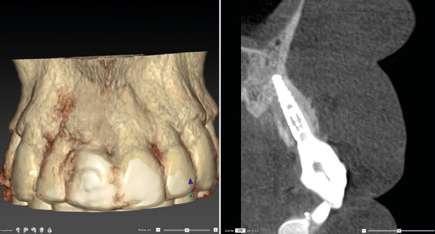

Diagnóstico, el clon digital

Por otro lado, es imprescindible y fundamental realizar un CBCT de la arcada a tratar para poder visualizar los tejidos duros y hacer una primera valoración del lecho implantario y de la patología existente.

Otra prueba imprescindible hoy en día para nosotros es la realización de un escaneado intraoral que nos aporte la información de los tejidos superficiales y fusionado con el CBCT nos permita valorar los tejidos blandos del paciente.

Para manejar todos estos datos vamos a necesitar de un software de diagnóstico y planificación digital como es el de DTX StudioTM Implant en el cual vamos a abrir tanto el CBCT como el escaneado intraoral y nos va a permitir fusionar ambas mayas utilizando la herramienta SMARTFUSION. En un caso como éste, donde tenemos un incisivo central, superior, derecho, fracturado que vamos a extraer debemos realizar previamente la extracción Virtual en el modelo digital para poder incorporarlo a la planificación de nuestro software.

En este caso, podemos ver que tenemos un defecto óseo vestibular, se trata de un defecto de una sola pared de la zona a implantar. Intentamos planificar un implante inmediato y observamos la posibilidad de tener un buen anclaje apical por lo tanto nuestra primera opción va a ser la realización de un implante post extracción con regeneración de la pared vestibular mediate xenoinjerto óseo e injerto de tejido conectivo para mejorar el biotipo.

na paciente de 35 años (Figura 1) fue remitida a la Clínica de Odontología Reconstructiva de la Universidad de Zúrich debido a una infección crónica en el diente 11 y con expectativas estéticas muy altas. El diente 11 había sufrido un trauma hace 10 años y había sido tratado con multiple endodoncias sin éxito. El diente presentaba un absceso bucal (Figura 2), una bolsa periodontal aislado de 9 mm, y una ausencia de la tabla vestibular ósea (Figura 3). El diagnóstico se estableció como una fractura radicular vertical, lo que resultó en un pronóstico pobre. El plan de tratamiento consistió en una extracción combinada con preservación alveolar, colocación de implante diferido con injerto de tejido conectivo, una corona cerámica implantosoportada en 11 y una nueva carilla de cerámica para el diente 21.

El diente 11 fue extraído (Figura 4), seguido por la preservación alveolar. Se realizó un injerto pediculado de espesor parcial rotado del paladar (Figura 5), junto con una membrana de colágeno reabsorbible, un xeno-injerto bovino y cianoacrilato sellando al alveolo (Figura 6). La provisionalización consistió en un puente adhesivo de resina con dos alas de metal. El alveolo se dejó cicatrizar durante 6 meses, después de los cuales se tomó una impresión digital así como un escáner CBCT (Figura 7). Se llevó